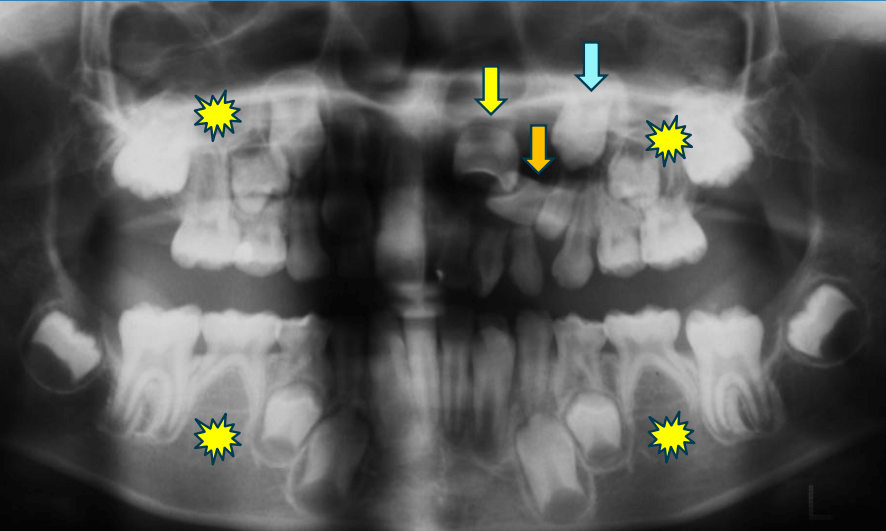

早期矯正治療 埋伏歯症例①

主訴 | 上顎の永久歯の位置がおかしいとのことで来院。萌出していない右上の前歯の状態に不安を抱えられていました。 |

---|---|

診断結果 | 8歳11か月の男児。早期対応が必要と判断されました。 |

治療内容 | 埋伏してる上顎右側をけん引するために、上顎にリンガルアーチを装着しました。 口腔外科医に開窓術を施術していただき、埋伏歯の牽引を開始しました。 |

治療後の経過 | 早期矯正治療終了後、3~4か月おきに定期検診を行います。 上下顎第2大臼歯(真中から7番目の永久歯)が生え揃い、上下顎骨の成長発育が落ち着いてから本格矯正治療を行います。 |

治療期間 | 動的治療期間:約3年2か月 |

治療費用 | 440,000円(税別) |